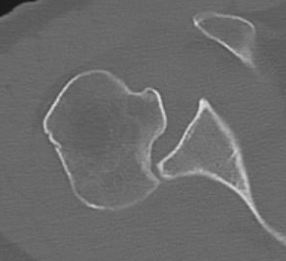

CT scan

Confirms dislocation

Reverse Hill Sachs

Humeral head defect

- caused by impaction of anterior humeral head on posterior glenoid

- intra-articular

- measured as a percentage of the articular surface

Lesser tuberosity fractures

Posterior glenoid fractures / bony bankart